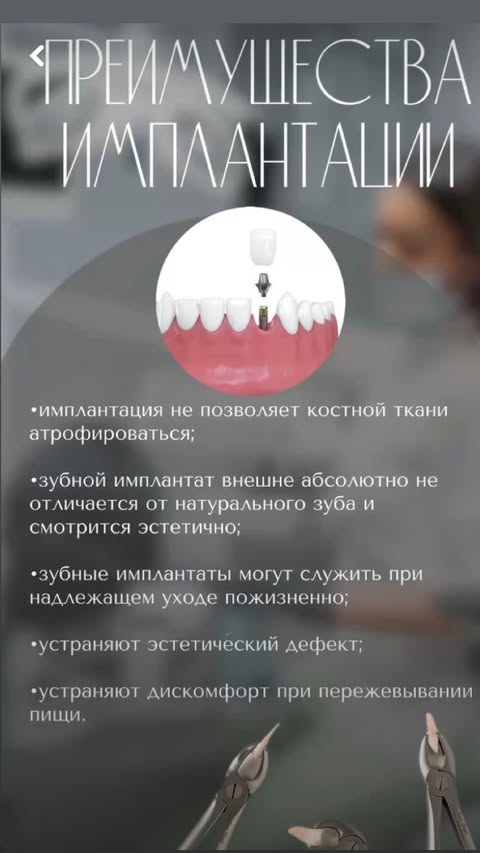

Терапия, ортопедия, хирургия, имплантация, ортодонтия, эстетическая реставрация — все в одном месте